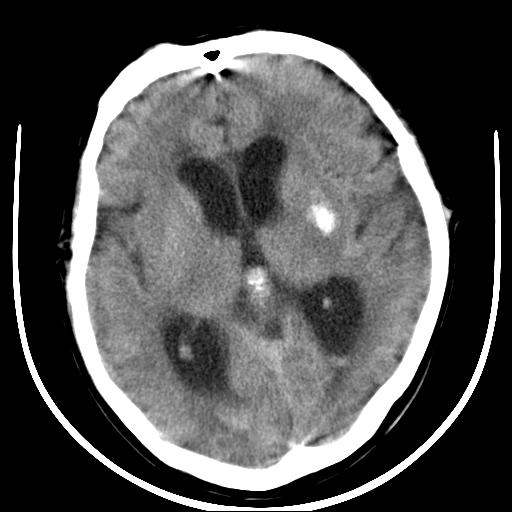

标题: CT16838:男58岁,意识不清2小时,请会诊出血部位该如何写。 [打印本页]

标题: CT16838:男58岁,意识不清2小时,请会诊出血部位该如何写。

1)脑干、左侧桥小脑臂及小脑蚓部出血破入蛛网膜下腔。2)左侧基底节区灶性出血,不排除钙化灶。3)脑室系统少量积血。4)脑积水。

(患者病情危重,出现不自主运动——是引起图像质量不佳的主要原因)

脑干左侧原发性脑出血破入脑室系统及蛛网膜下腔出血伴梗阻性脑积水。左侧基底节区原发性脑出血。脑萎缩。

脑干左侧原发性脑出血破入脑室系统及蛛网膜下腔出血伴梗阻性脑积水。左侧基底节区原发性脑出血可能性大,钙化不除外。